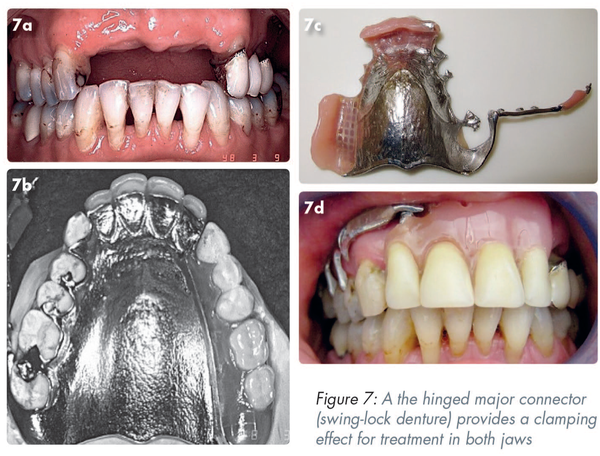

Treatment in both jaws

In essence, the hinged major connector (swing-lock denture), duplicates the clamping effect seen in Figures 5c and 5d. The teeth that complete the anterior bounded saddle (Figure 7a) are added to the full coverage chrome cobalt plate (Figure 7b). A mobile arm on the right-hand side attached to the framework (Figure 7c) clips into a lock and acts both as a splint and a retainer for the denture.,, (Figure 7d) As the framework covers a wide area of the gingival tissues it requires special attention for plaque control. Tooth support is essential to avoid damage to the supporting tissues. Patients will require some degree of manual dexterity to close/open the clasp.